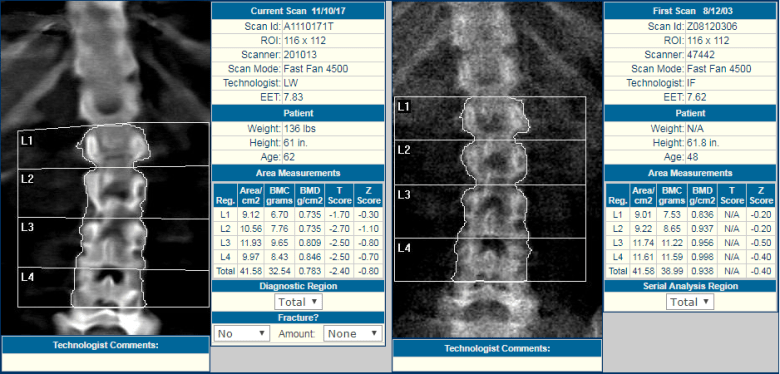

While DXA bone density scan images should not be used for diagnostic purposes, they are instrumental in determining the consistency of serial measurements. Is the patient positioned properly? Are the regions of interest (ROIs) consistent with prior scans? What is the technical quality of the scans?

BoneStation’s review process is designed to highlight key aspects for interpretation. Prior scans are easily visible. ROIs may be viewed both visually and numerically. Technical quality of scans must be specified and may also appear on the report.